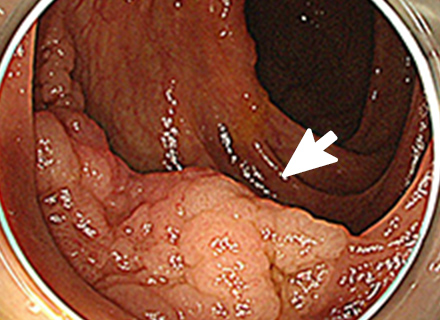

大腸ポリープまたは早期大腸がんの内視鏡治療

良性のポリープや早期がんの中でも粘膜だけにとどまっているもの、粘膜下層へわずかに広がっているものが内視鏡治療の適応となります。 小さなポリープに対しては、鉗子でつかみながら高周波電流を用いて病変の根もとを焼き切ります(ホットバイオプシー)。 茎のあるポリープに対しては、輪の形のスネアを茎の部分でしめ、高周波電流を用いて切断します(ポリペクトミー)。 茎のない病変に対しては、内視鏡的粘膜切除術(EMR)や内視鏡的粘膜下層剥離術(ESD)などを行います。

| 下部消化管 ESD | 20 | 22 | 19 | 19 | 33 | 38 | 46 | |||||||